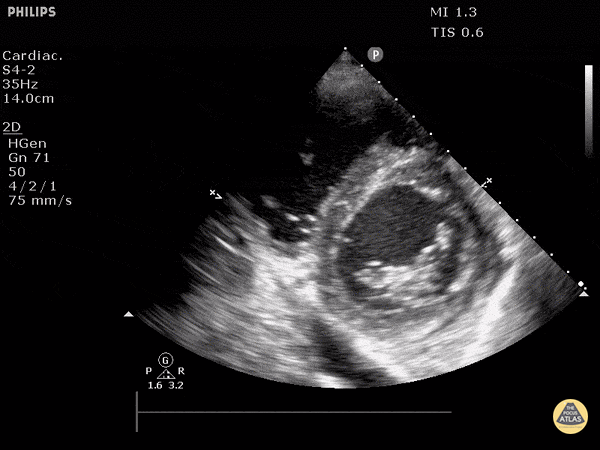

Left Ventricular Dysfunction - Moderately Reduced Ejection Fraction - Basal Parasternal Short Axis

This image is a basal parasternal short axis view demonstrating a moderately reduced ejection fraction Justin Bowra MBBS, FACEM, CCPU Emergency Physician, RNSH et al. (Dr. Vahtrick)